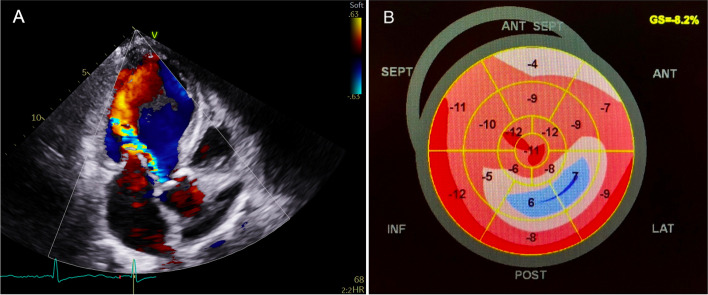

Background: Aortic regurgitation (AR) has an important impact on myocardial mechanics and recent studies have proved the value of global longitudinal strain (GLS) in the assessment of its severity and prognosis. Our purpose was to assess if the direct impact of the regurgitant jet on the myocardial wall could affect regional longitudinal strain.

Methods: Eighty patients with chronic moderate/severe AR were retrospectively studied. Patients were considered to have a jet-related longitudinal strain reduction when the myocardial segments directly impacted by the jet had their longitudinal strain reduced by at least 30% compared to nonaffected segments. AR severity, left ventricular (LV) size and function were compared according to the presence/absence of this regional pattern. For those who underwent surgery, postoperative regional and global LV function was also analyzed.

Results: A pattern of regional longitudinal strain impairment was identified in 43% of patients, with a regional reduction (in median) of 10 percentage points in absolute strain values in the segments impacted by the jet, compared to nonaffected segments. In the subgroup who underwent surgery, this pattern became attenuated after surgery. Patients with regional longitudinal strain impairment were less likely to improve GLS after surgery (10% vs. 38% improved GLS by at least 2.5%, P = 0.049).

Conclusions: To our knowledge, this study identifies for the first time, a link between the location of the impact of the regurgitant jet in AR and regional longitudinal strain impairment. The presence of this regional pattern might be associated with worse postoperative LV recovery.